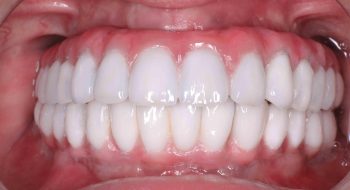

Tooth implant procedure (Dental implant procedure)?

Tooth implant surgery is a procedure that replaces missing tooth or damaged tooth with screw like bio-compatible material called titanium or zirconium. The damaged tooth is removed and the tooth implant is placed in the jaw bone under anaesthesia by an implantologist. Once the tooth implant is placed in the jaw bone, it is allowed to heal and osseointegrate (fuse with the surrounding bone) to become part of the human body. After 4-6 months’ time, the crown is placed on the implant to restore the functionality of the tooth.